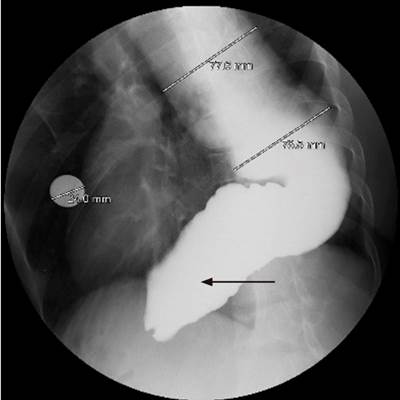

During the esophagogastroduodenoscopy, traces of food content were found in the esophagus. The esophageal body was severely dilated, tortuous, with angulations, and the gastroesophageal junction was punctiform, although it was difficult to pass through (Figure 3). Barium esophagogram revealed a severely dilated esophageal body, with the lower esophagus in a sigmoid-likepattern (Figure 4).

Figure 4 Barium esophagogram. Gastroesophageal junction below the left hemidiaphragm, which shows an alteration in lower esophageal sphincter relaxation that causes delayed gastric emptying. Sigmoid appearance of distal esophagus (thin arrow). Source: Gastroenterology Unit. Hospital Universitario San Ignacio. Bogotá D.C. Colombia.